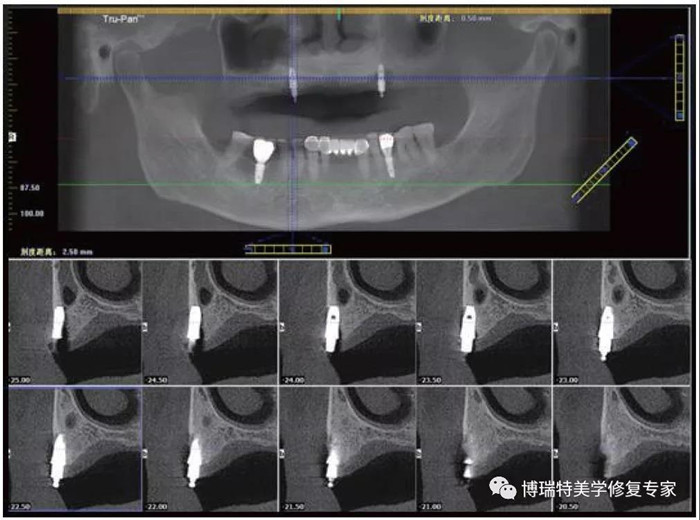

1. 种植术后

KM宽度≥2 mm可减缓MBL降低

美国和巴西的一项联合研究显示,种植体周围角化黏膜(KM)的宽度对边缘骨水平(MBL)、菌斑积聚、周围组织炎症及刷牙不适有影响。因此,种植体周围的KM≥2 mm的情况可能对种植体周围组织有保护作用。

该研究的目的是评估种植体周围角化黏膜对边缘骨水平、种植体周围组织健康和刷牙不适的长期影响。在2013年1月~10月的维持性访问期间,研究共招募了80例患者,并按种植体周围的角化黏膜宽度分为两组:宽组(KM≥2 mm)和窄组(KM<2 mm)。

在4年随访中,重新评估MBL、改良菌斑指数(MPI)、探诊深度(PD)、临床附着水平(CAL)、探诊出血(BOP)和刷牙不适(BD),并与最初评估结果进行比较。采用曼·惠特尼检验和多水平模型进行统计分析。

结果为,在第4年回访时,共54例患者(202个种植体)。窄组MPI(0.91±0.60)、BOP(0.67±0.21)和BD(12.28±17.59)均高于宽组(0.54±0.48、0.56±0.26和4.25±8.39)。而且窄组的种植体周围骨吸收量(0.26±0.71)高于宽组(0.06±0.48)。多水平模型分析表明,KM的宽度和作用时间对MBL有显著影响。